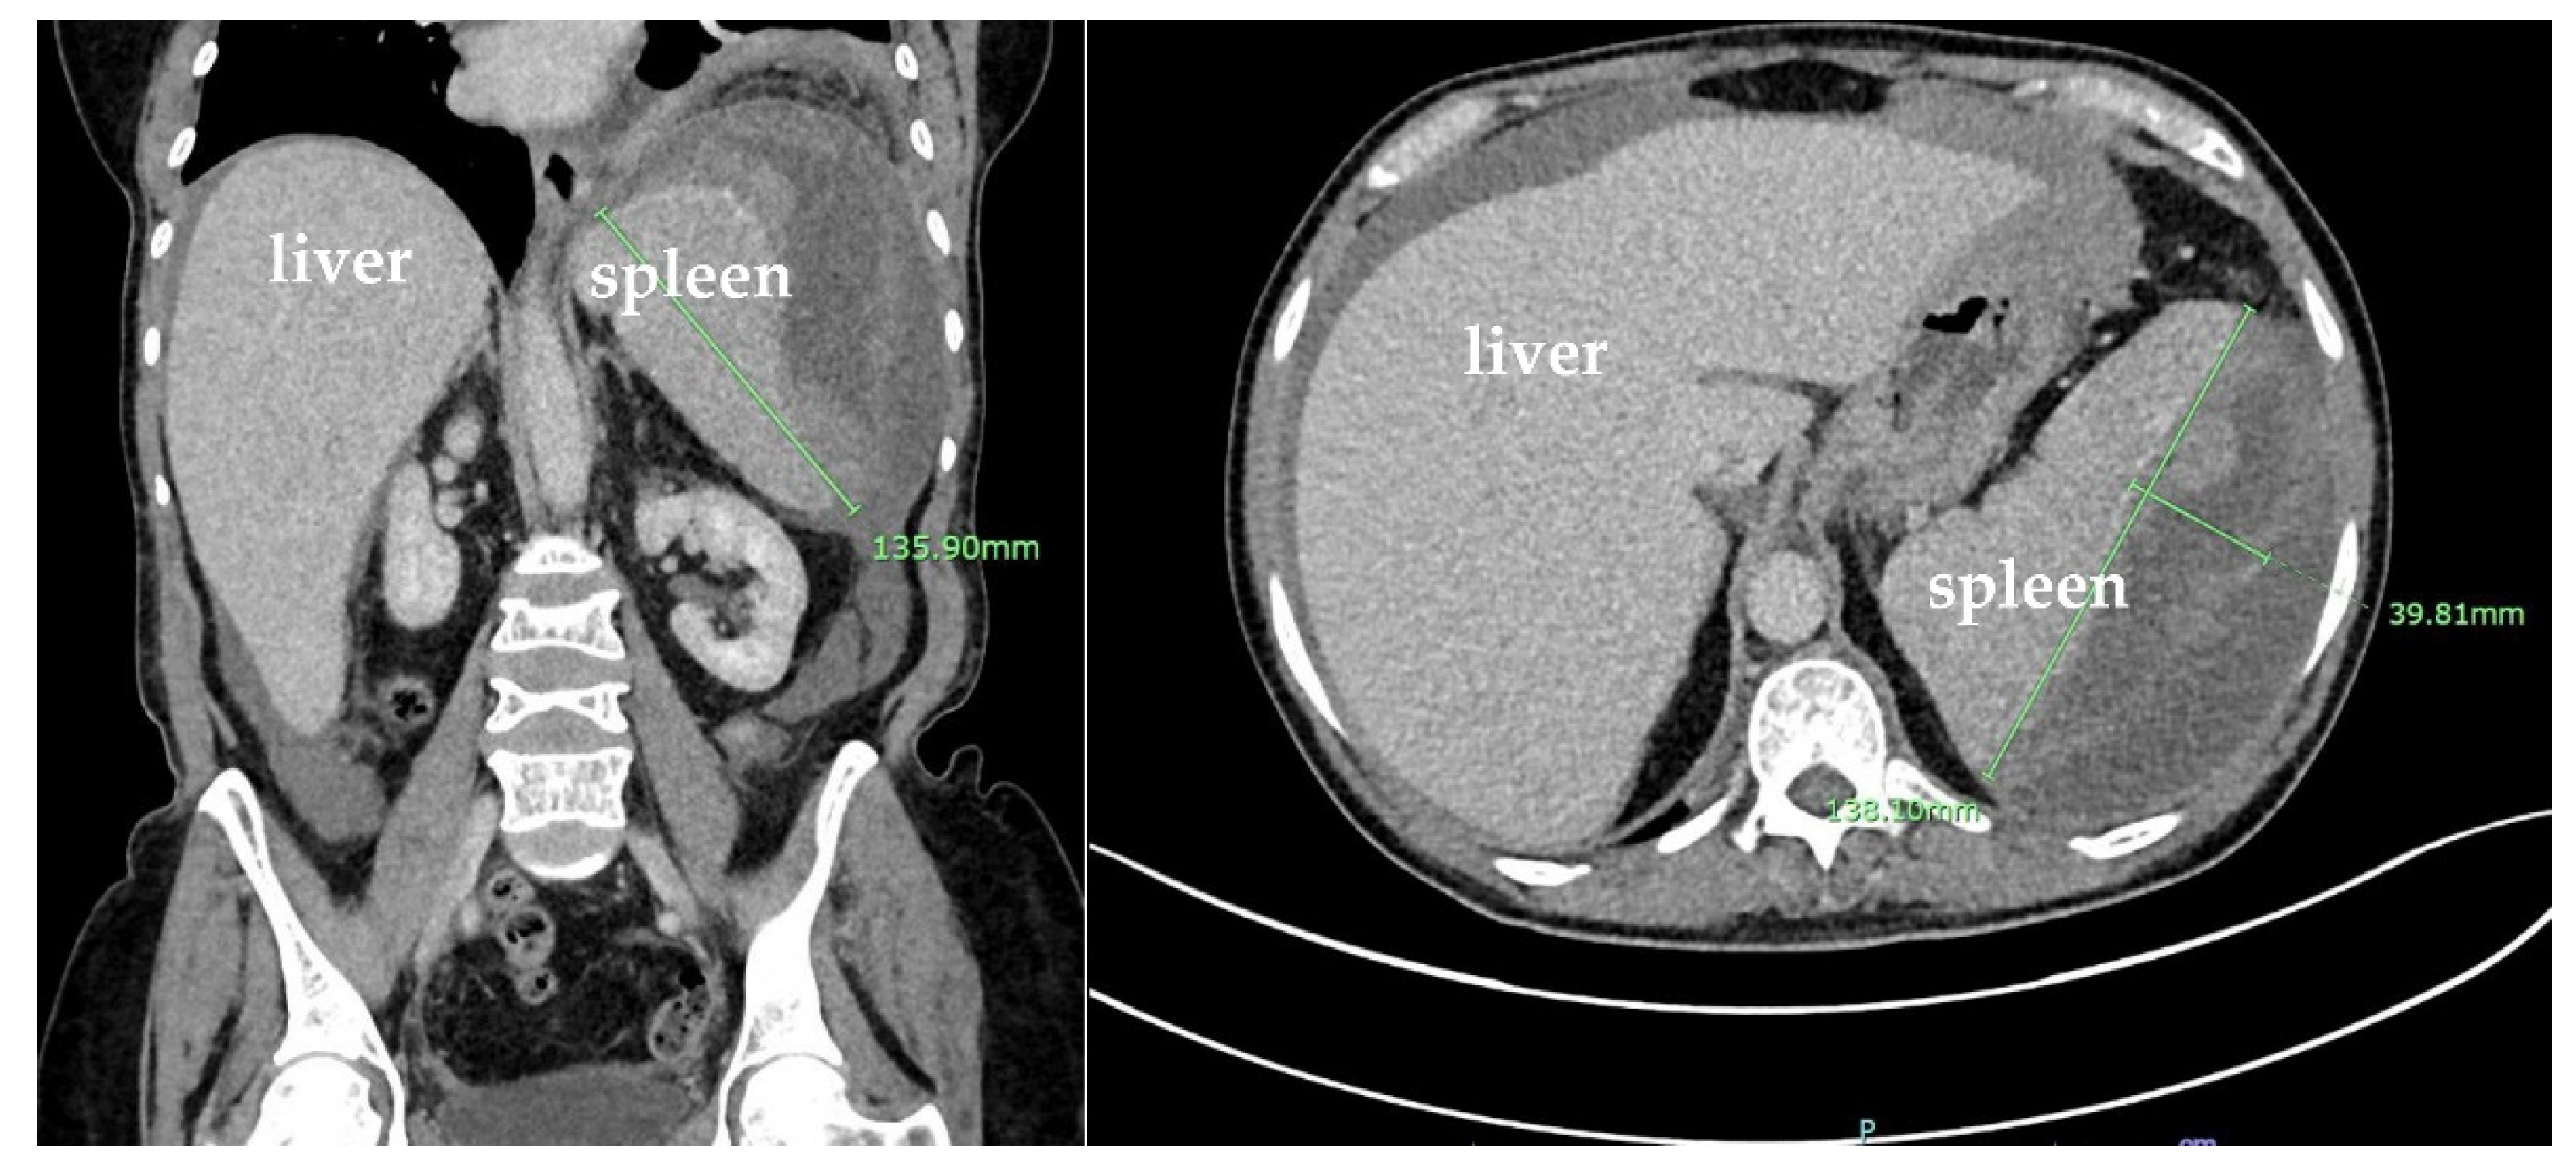

3. Case Presentation

| Buzalewski et al., 2019 [8] | USA | Case report, 68-year-old male | Most common cause of atraumatic splenic rupture is hematologic processes; amyloidosis is rare | Weakness: 1 patient, multiple comorbidities, multiple prior treatments, multiple hematologic diagnoses | CT on admission showed splenomegaly and splenic hematoma, treated with exploratory laparotomy and splenectomy; multiple post op complications; Dx with AL amyloidosis and MM |